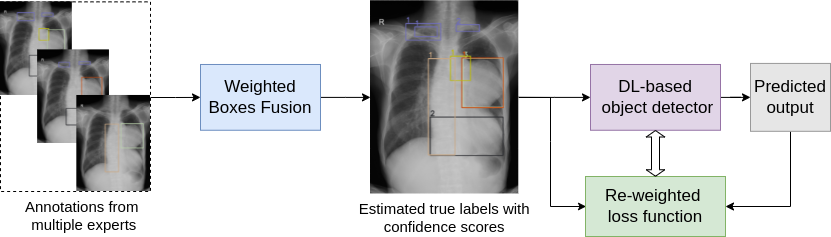

This work aims at addressing a fundamental question “How to train a deep learning-based detector effectively from a set of possibly noisy labeled data provided by multiple annotators?” [12]. To this end, we introduce a novel approach that learns from multiple expert annotators to improve the performance of a deep neural network in detecting abnormalities from chest X-ray images. The proposed approach, as visualized in Figure 1, consists of two stages. The first one is truth inference using Weighted Boxes Fusion (WBF) algorithm [13] to estimate the true labels and their confidence scores. The second stage is to train an object detector on estimated labels with a re-weighted loss function using implicit annotators’ agreement, which is represented by the estimated confidence scores. For evaluation, we first simulate and test the proposed approach on a multiple-experts-detection dataset from MNIST [14] called MED-MNIST. We then validate our approach on a real-world chest X-ray dataset with radiologist’s annotations. Experiments on those scenarios demonstrate that the proposed approach provides better detection performance in terms of mAP scores than the baseline of treating multiple annotations as ground truth and the ensemble of models supervised by individual expert annotations.

Given a set of N𝑁N training images {𝐱i}i=1Nsuperscriptsubscriptsubscript𝐱𝑖𝑖1𝑁\left\{\mathbf{x}_{i}\right\}_{i=1}^{N} with corresponding bounding box annotations {y~i(r)}i=1Nsuperscriptsubscriptsuperscriptsubscript~𝑦𝑖𝑟𝑖1𝑁\left\{\tilde{y}_{i}^{(r)}\right\}_{i=1}^{N} from multiple annotators where y~i(r)superscriptsubscript~𝑦𝑖𝑟\tilde{y}_{i}^{(r)} denotes the label for example 𝐱isubscript𝐱𝑖\mathbf{x}_{i} given by annotator r𝕊(R)𝑟𝕊𝑅r\in\mathbb{S}(R), which 𝕊(R)𝕊𝑅{\mathbb{S}}(R) is a set of R𝑅R different expert annotators. In this study, we make use of those expert annotations {y~i(r)}i=1Nsuperscriptsubscriptsuperscriptsubscript~𝑦𝑖𝑟𝑖1𝑁\left\{\tilde{y}_{i}^{(r)}\right\}_{i=1}^{N} to estimate a single set of true labels with confidence scores {𝐲i;ci}i=1Nsuperscriptsubscriptsubscript𝐲𝑖subscript𝑐𝑖𝑖1𝑁\left\{\mathbf{y}_{i};c_{i}\right\}_{i=1}^{N}. We then train a supervised object detector with the estimated labels using the proposed re-weighted loss function. In order to evaluate the effectiveness of the proposed method, we use a gold-standard test set 𝒯={(𝐱(j),𝐲(j))}j=1M𝒯superscriptsubscriptsuperscript𝐱𝑗superscript𝐲𝑗𝑗1𝑀\mathcal{T}=\left\{\left(\mathbf{x}^{(j)},\mathbf{y}^{(j)}\right)\right\}_{j=1}^{M} containing M𝑀M examples. In medical imaging scenarios, where the true labels are not available, we obtain the gold-standard test labels 𝐲(j)superscript𝐲𝑗\mathbf{y}^{(j)} from the consensus of a group of experiences radiologists. Figure 1 below shows an overview of the proposed method.

Figure 1: Illustration of the proposed approach that aims to build a deep learning system for abnormal detection on medical scans from multiple expert annotators. The training process contains two stages. The first stage focuses on truth inference, in which it estimates the true labels using the WBF algorithm [13] with the implicit annotator’s agreement as confidence scores. The second uses the estimated confidence scores to train a deep learning-based detector using a re-weighted object detection loss function. To provide abnormality analysis during the testing phase, only the fully trained image detector is required.